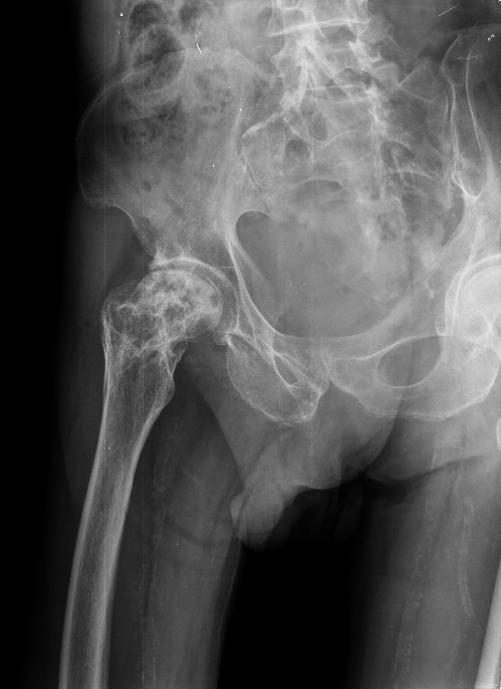

Una caída ocasional como consecuencia de un resbalón en la helada matutina de este invierno tan frío, llevó consigo que Sara, una paciente de 87 años se fracturara la cadera. La primera atención se la proporcionó el 061 en su ambulancia medicalizada, tras la inmovilización se procedió a su trasporte al hospital de referencia donde tras la verificación y comprobación radiológica se operó. La cirugía fue compleja, realizándose una hemiartroplastia. Pasados tres meses de la cirugía persistía el dolor y el callo de fractura no se correspodía al tiempo transcurrido, proponiéndole su médico traumatólogo una nueva cirugía que posiblemente implicaría una prótesis permanente en su cadera. En este estado acudió al médico homeópata, su idea era intentar librarse de una cirugía que no deseaba. Verificadas las pruebas de imagen y confirmados sus síntomas dolorosos a la movilización activa y pasiva se prescribió Calcárea phosphórica 30 CH, toma diaria de un gránulo y nueva valoración radiográfica en un mes. Al mes el callo de fractura se había iniciado y lo que se evidenciaba en la placa, también se percibía en la evolución del cuadro clínico de la paciente, que se encontraba mejor. El traumatólogo que vio la radiografía, indicó espera ante la evolución del cuadro. Siguió la paciente tomando el remedio tal y como se ha indicado y a los dos meses de iniciada la toma se verificó un callo bien consolidado, fue en ese momento cuando se retiró la férula y se inició la rehabilitación que en este caso precisó de tres meses para recuperar la masa muscular perdida.

Al respecto de Calcárea phosphórica nos comenta Phatak: Afecta la NUTRICION de huesos y glándulas; los huesos se vuelven blandos, delgados y quebradizos; promueve la osificación de los huesos en fracturas de no unión. Vijnowsky apostilla: Siendo el principal constituyente óseo, su acción fundamental se manifiesta a nivel de los huesos. Formación muy lenta o tardía del callo óseo en los extremos óseos de las fracturas; ayuda a acelerar su formación, y puede prescribiese preventivamente desde el momento de la fractura. Exostosis, osteofitos, enfermedades oseas. Atendiendo por tanto a estos criterios, es posible que lo razonable hubiera sido tratar a Sara desde el comienzo de  la aparición de su patología con dicho remedio. Hoy día en todas las fracturas, del tipo que sean, para mí es un remedio indicado desde el primer momento, siempre lo hago del mismo modo: Prescribo Calcarea phosphórica 30 CH gránulos uno diario hasta la verificación por Rx del callo activo y consolidado.